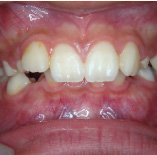

セラミック治療

こんな歯並びでもご心配なく。矯正という方法をとらなくても、ここまできれいに治せるんです。見た目だけでなく歯ブラシもやり易くなりました。笑顔に自信がつきますよ。

- 施術前

- 施術後